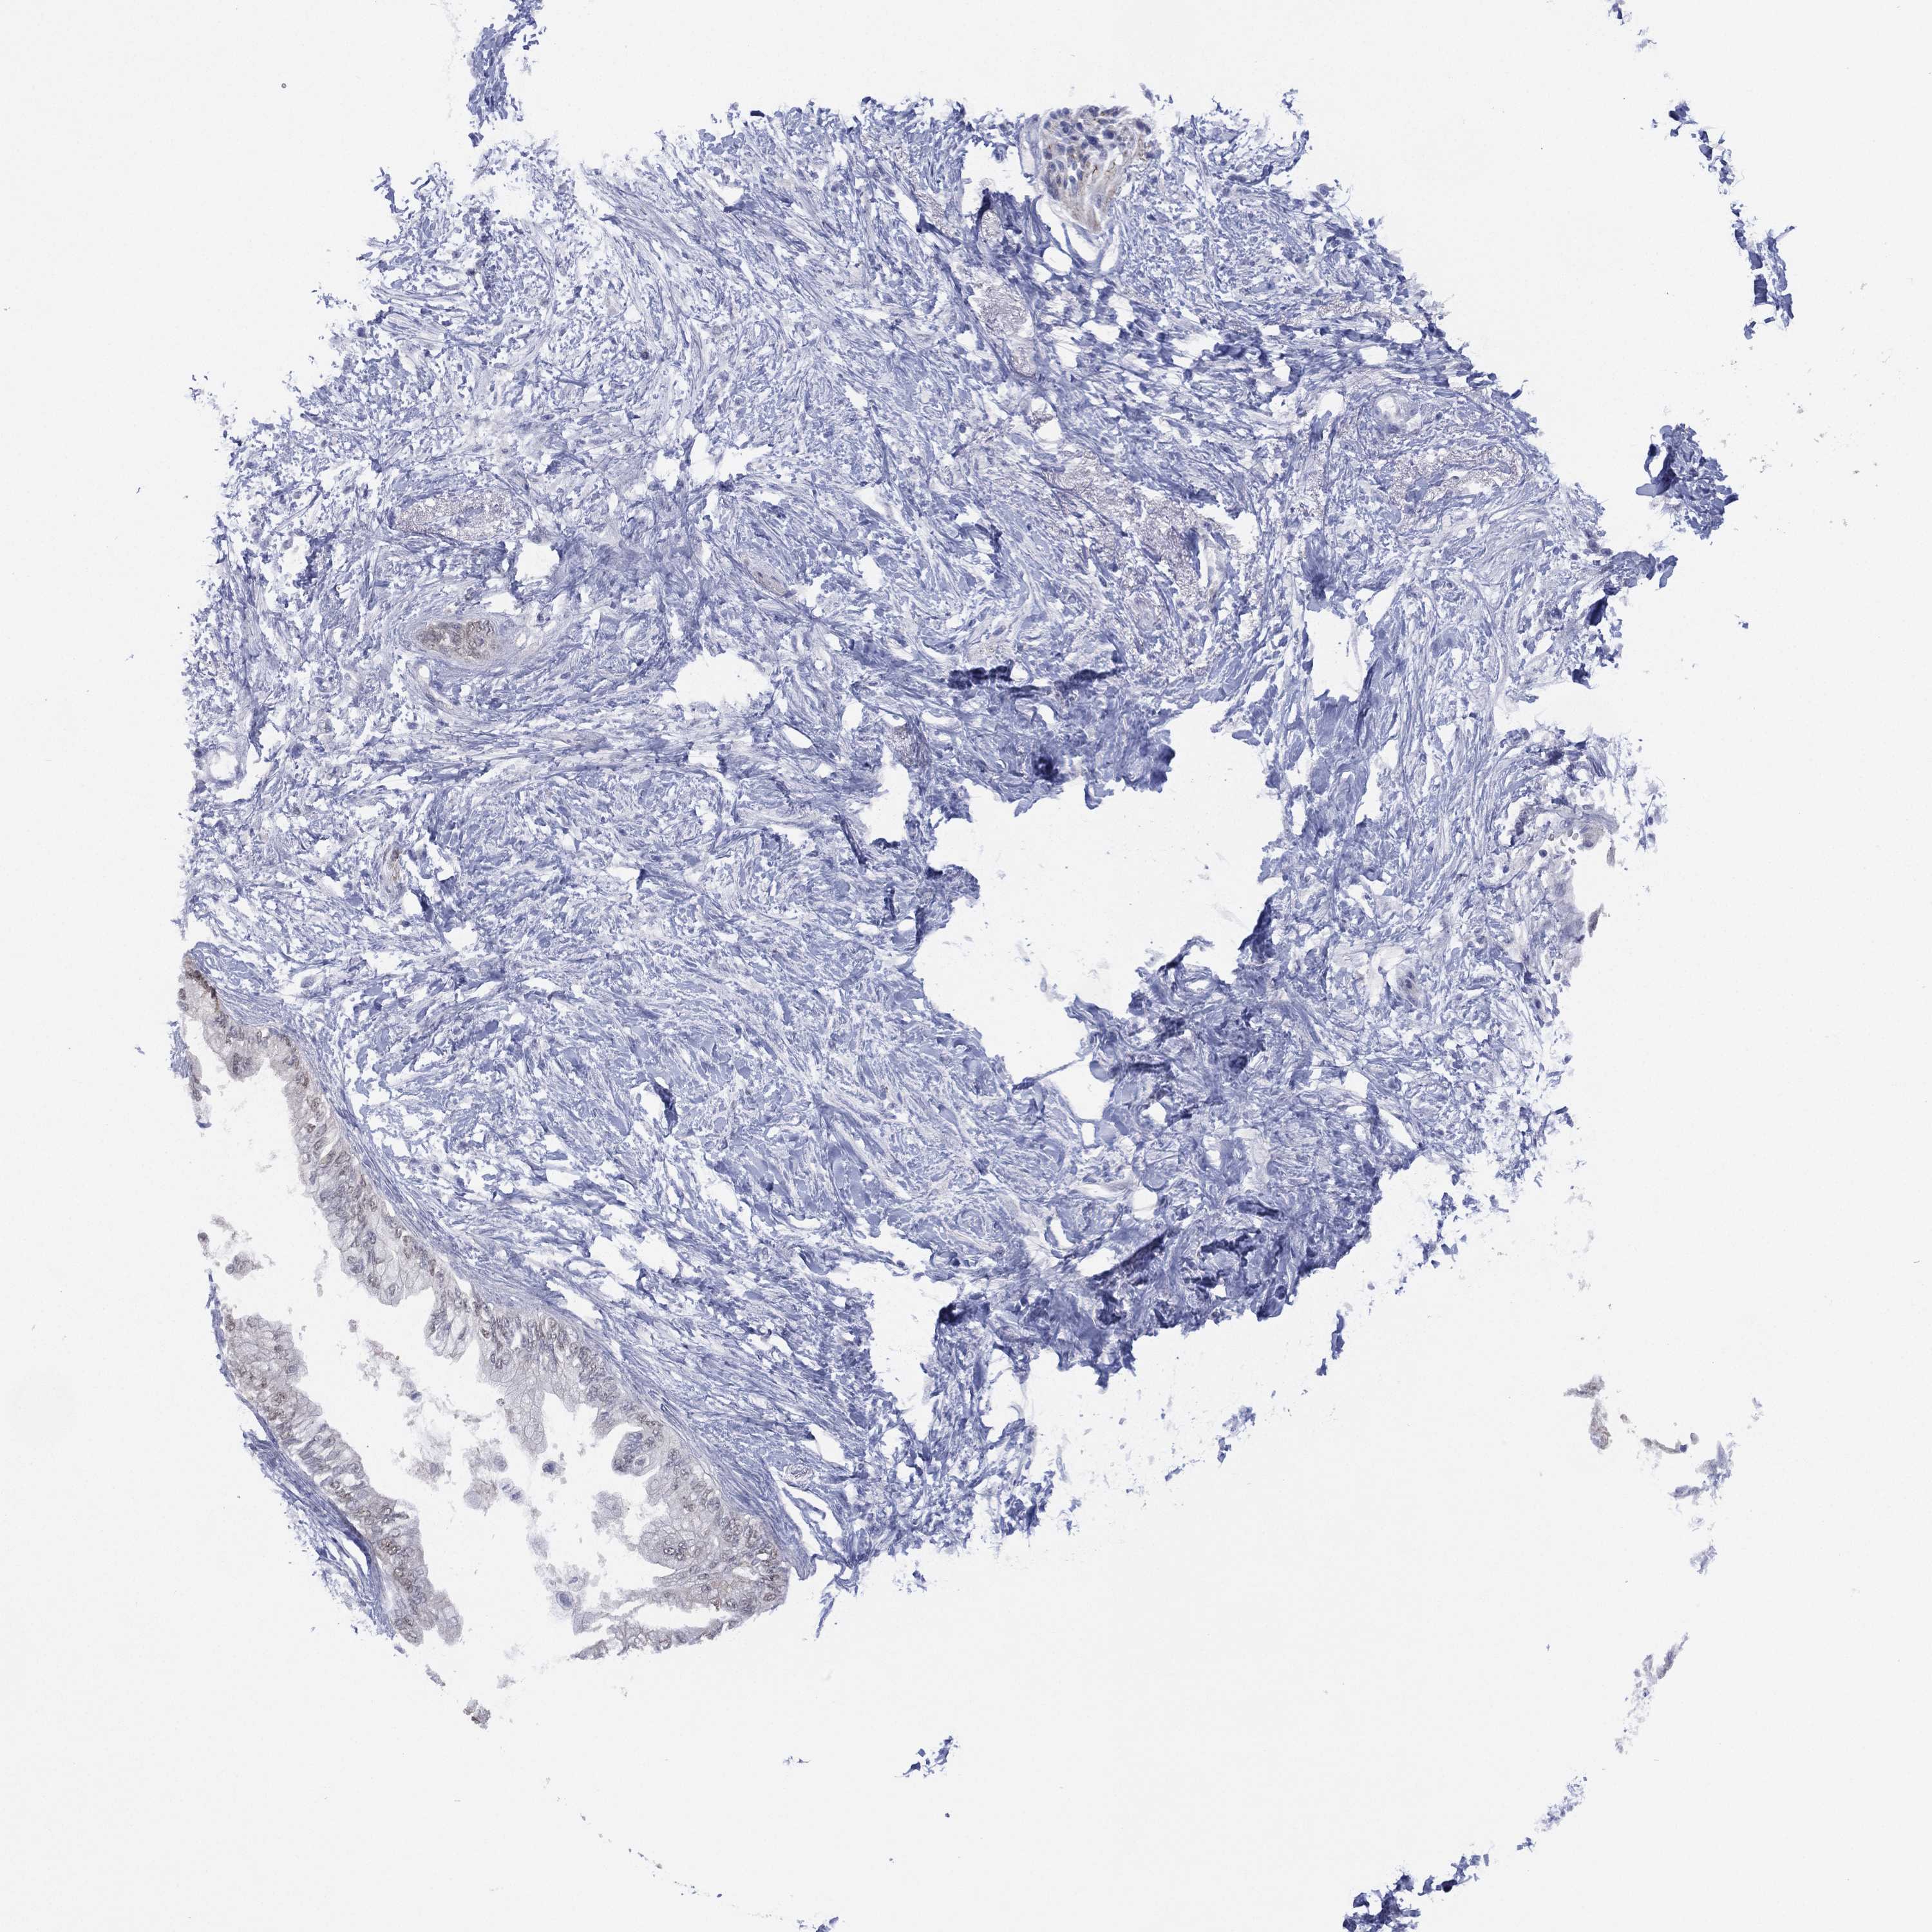

PANCREATIC CANCER - Protein expressioni

A mouse-over function shows sample information and annotation data. Click on an image to view it in a full screen mode. Samples can be filtered based on level of antibody staining by selecting one or several of the following categories: high, medium, low and not detected. The assay and annotation is described here.

Note that samples used for immunohistochemistry by the Human Protein Atlas do not correspond to samples in the TCGA dataset.

Antibody stainingi

Antibody staining in the annotated cell types in the current human tissue is reported as not detected, low, medium, or high, based on conventional immunohistochemistry profiling in selected tissues. This score is based on the combination of the staining intensity and fraction of stained cells.

Each image is clickable and will lead to virtual microscopy that enables deeper exploration of all samples and also displays staining intensity scores, fraction scores and subcellular localization as well as patient and tissue information for each sample.

Antibody HPA006308

Antibody HPA071064

Staining

High

Medium

Low

Not detected

Intensity

Strong

Moderate

Weak

Negative

Quantity

>75%

75%-25%

<25%

None

Location

Nuclear

Cytoplasmic/membranous

Cytoplasmic/membranous,nuclear

Adenocarcinoma, NOS

Adenocarcinoma, metastatic, NOS